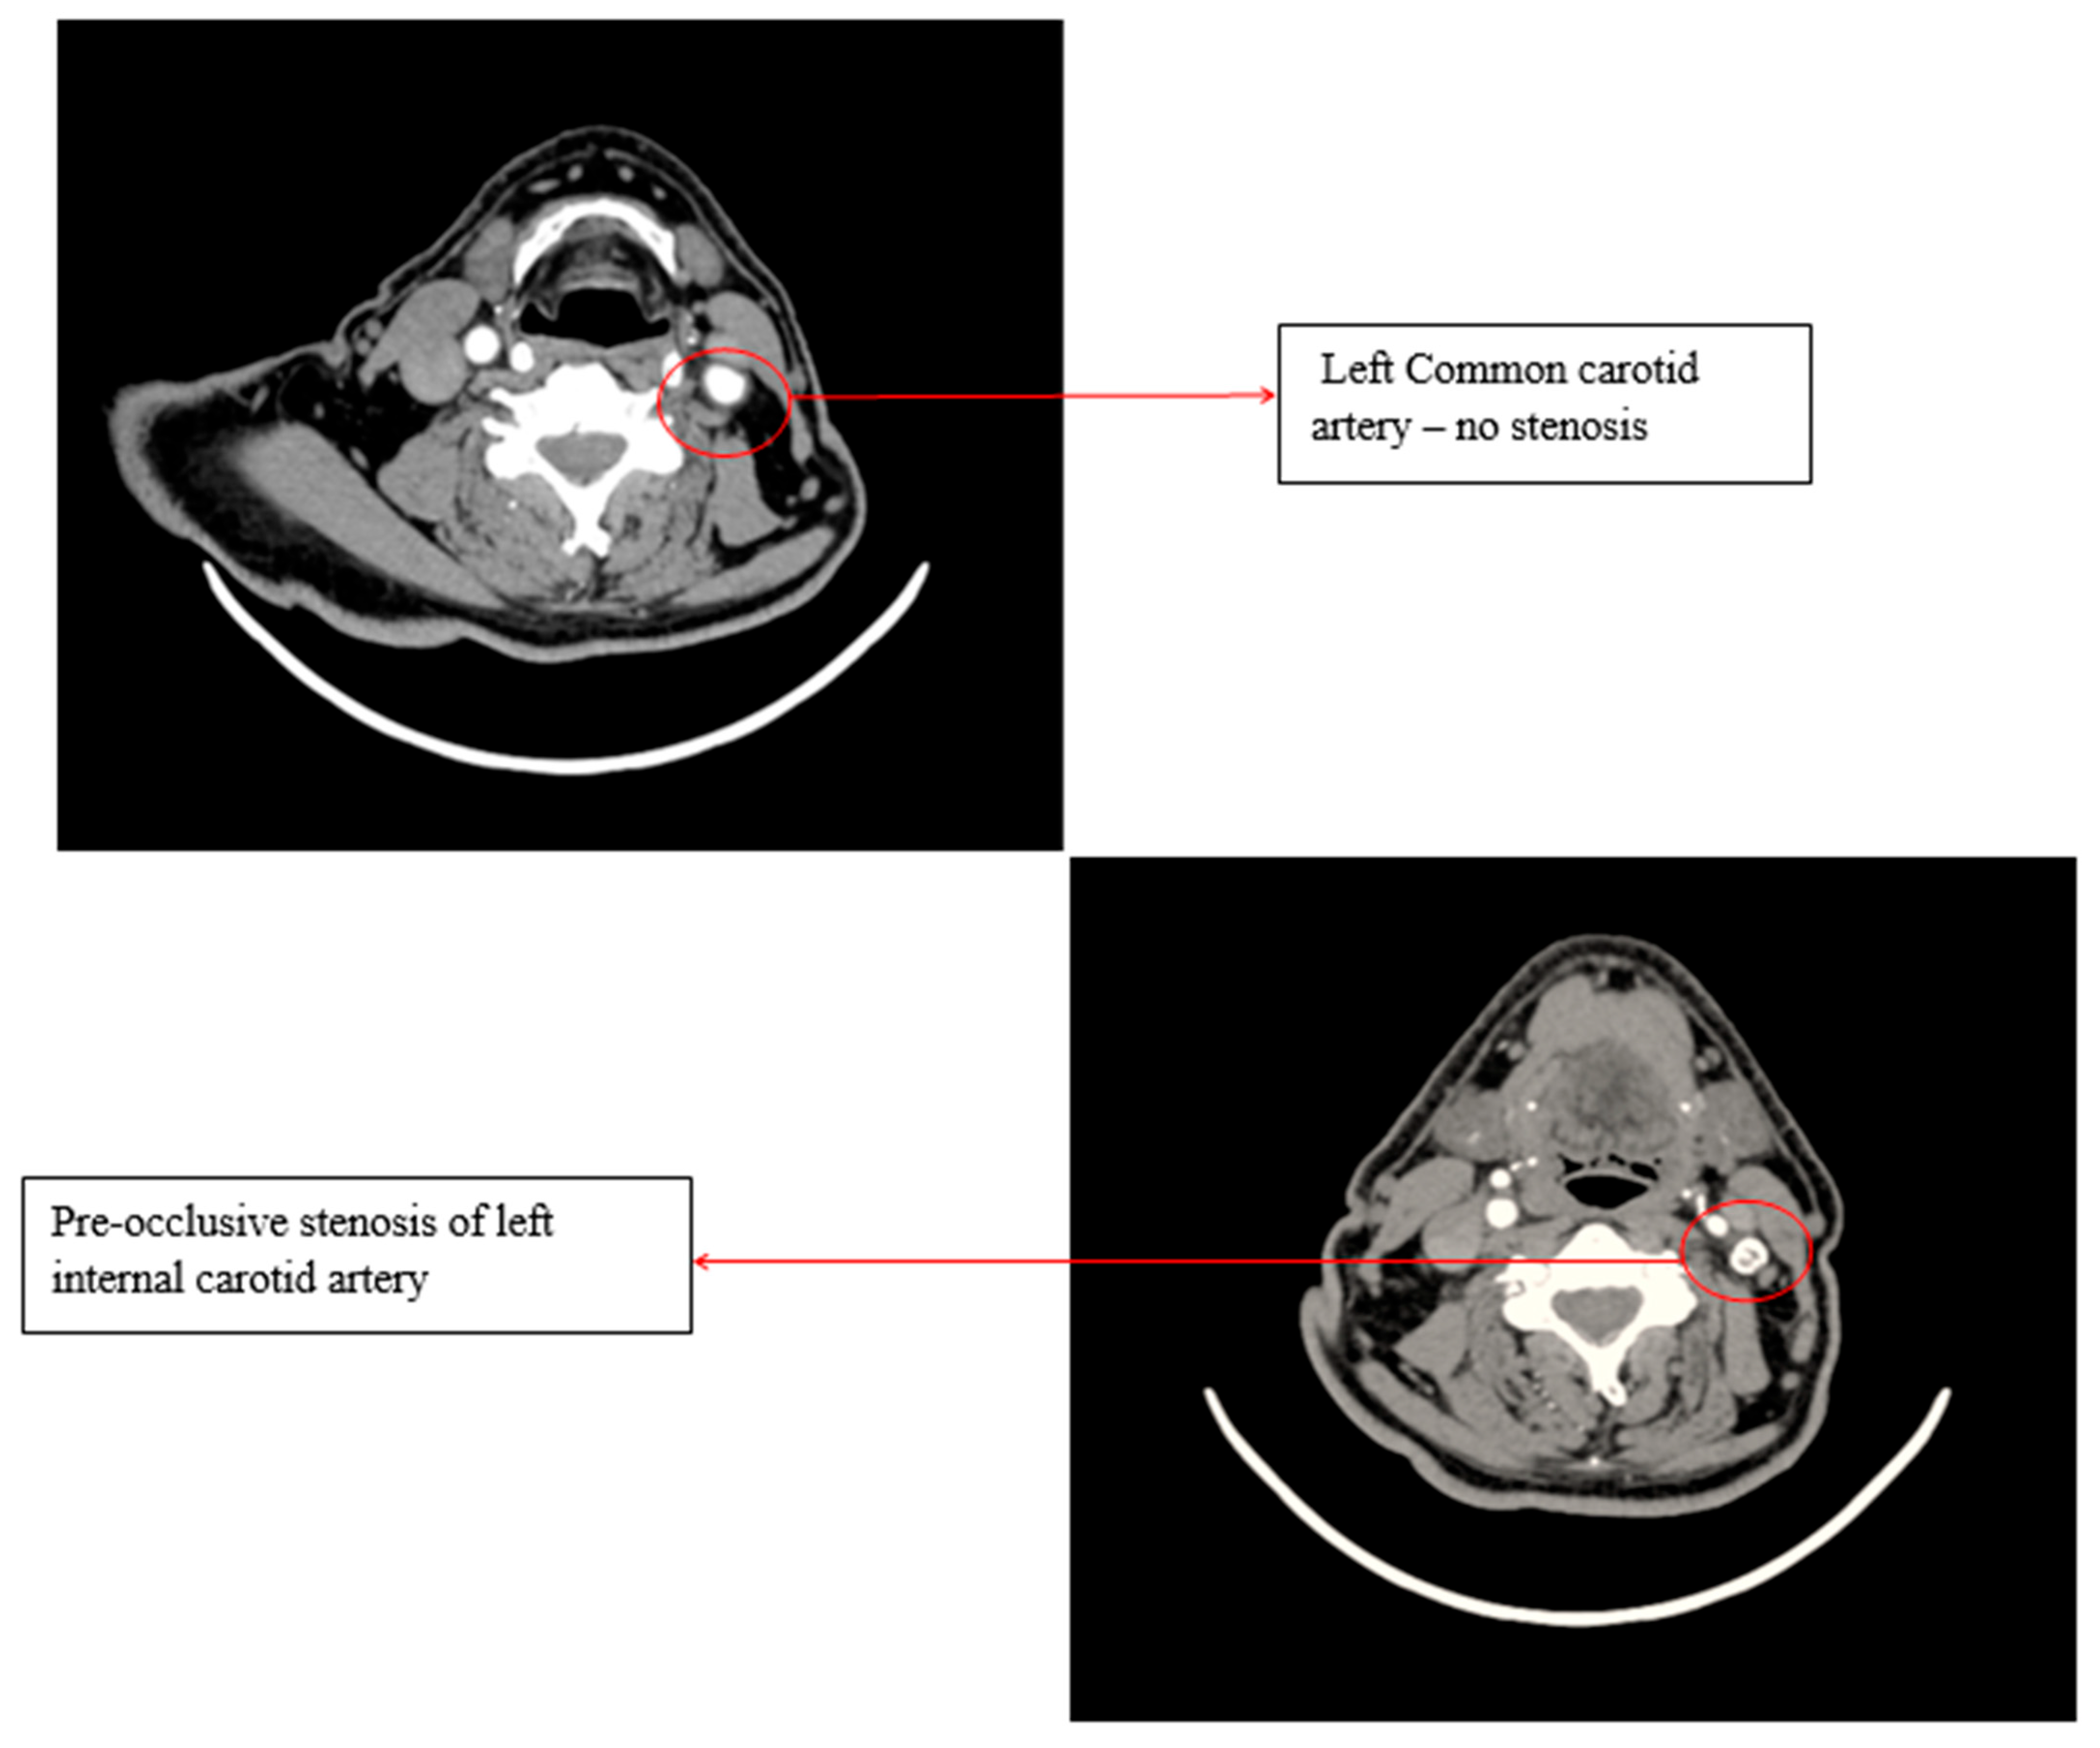

Unusual Evolution of Carotid Atherosclerosis in a Patient。Bilateral Large Vessel Occlusion Causing Massive Ischemic。701_2021_4754_Fig5_HTML.png。こちらの商品は裁断済商品になります。脳神経外科 脳血行再建の理論と実際。【タイトル】本書は「ENCYCLOPAEDIA of OCCLUSION」として知られ、咬合に関する包括的な情報を提供します。ピンズラーAmerican English Ⅰ。- タイトル: ENCYCLOPAEDIA of OCCLUSION- 出版社: The SHORIN Ltd.- 言語: 日本語- 状態: 経年劣化ありご覧いただきありがとうございます。Surgical occlusion of middle meningeal artery in treatment。購入後ScanすればiPadなどでいつでもどこでも読む事ができます。また再度メルカリに出品することができます。GPのためのアライナーシミュレーションガイド : これだけは覚えよう!歯科矯正…。歯科医学大事典 2巻~総索引。【出版社】この本はThe SHORIN Ltd.から出版されており、信頼性の高い資料です。【内容】咬合に関する詳細な知識を求める専門家や学生にとって、貴重なリソースとなるでしょう。カパンジー機能解剖学 II 下肢。メイトランド脊椎マニピュレーション。